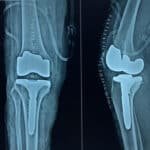

Joint replacement surgery is a surgical method of replacing the joint with an artificial or prosthetic joint, because the original joint is damaged or worn out. The treatment is very effective in patients with advanced arthritis, a fracture, or damage to a joint that cannot be managed with non-operative measures. We are recognized as the best joint replacement surgery orthopedic hospital in Madurai, able to complete your knee and hip replacement, regardless of your situation, using the best joint replacement techniques and facilities.

- Revision Joint Replacement in Madurai- When a patient contracts a second surgery after a knee replacement surgery.

- Revision Joint Replacement – For patients who have already undergone knee replacement surgery and need a second knee replacement.

Advanced Technology in Joint Replacement

At Cura Ortho Centre, we utilize advanced robotic joint replacement in Madurai and minimally invasive techniques, advocate for.

- More precise procedures.

- Less blood loss and reduced scarring.

- Better pain management, post-operatively.

- Faster recovery with a quicker return to daily activities after your joint replacement surgery.